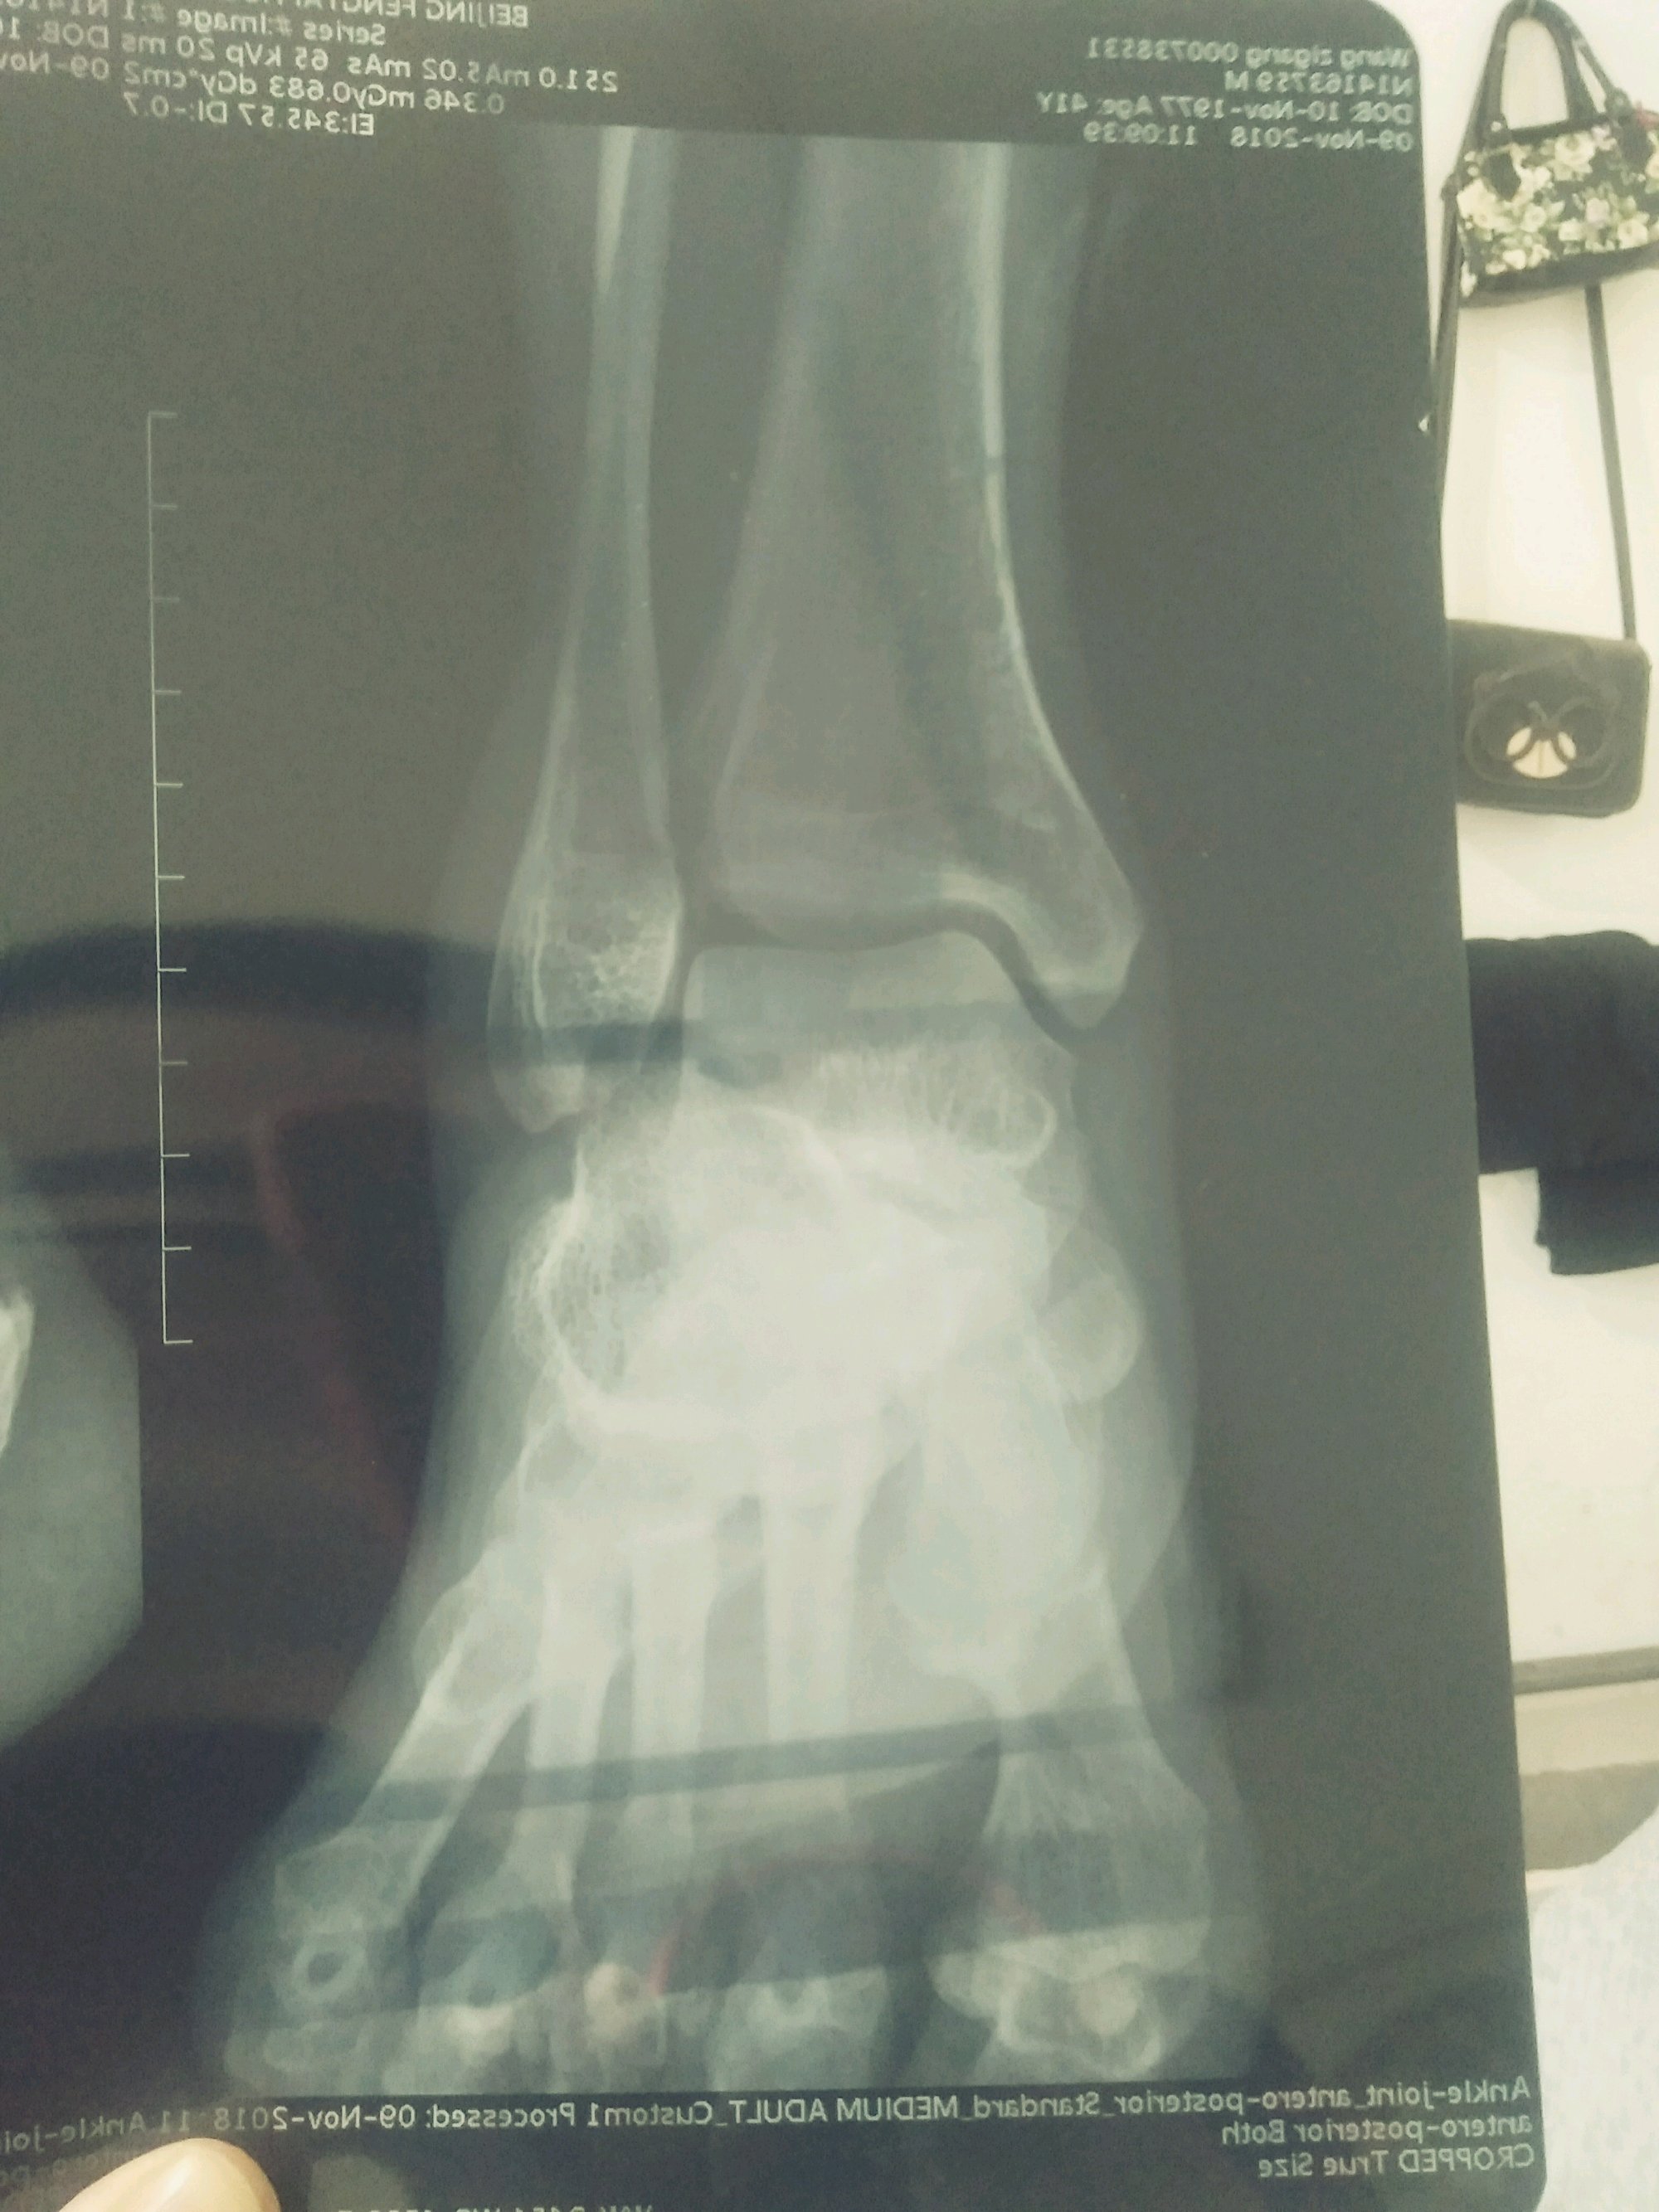

帮我看看这三这片子是怎么回事儿?我看不出来

脚背上的骨关节是不是移位了,跟骨距骨附骨有点骨裂吧

医生说是跟骨的 轴围的关节面骨折。

这个是怎么受伤的呢,这是横向冲击受伤的吗,

下楼梯歪脚。

哦,看见了,对对,是骨折了,这个可以保守的,

保守治疗两周骨折不连续才做的手术。